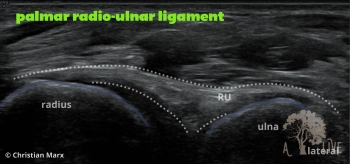

carpal ligaments